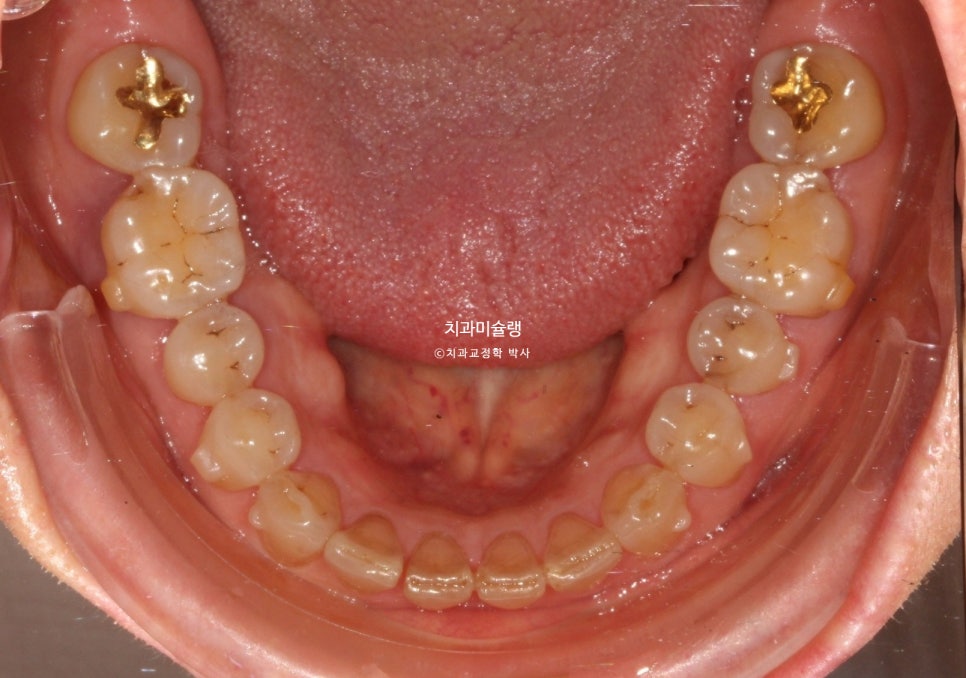

그에비해 아래앞니는 틈도 없고 틀어짐도 경미하죠.

어금니는 배열이나 교합상 문제가 없습니다.

또한 작은어금니부터 큰어금니 까지는 위치를 잠궈놓고 앞니만 움직이는 치료계획을 세우는게 좋습니다. 이렇게 하면 앞니를 제외한 치아들은 교정기간 내내 단 0.1mm의 이동도 없이 교합이 그대로 유지되며, 그만큼 교정치료로 인한 교합 변화로 인한 불편감도 적고 무엇보다 잇몸 부담이 적습니다.